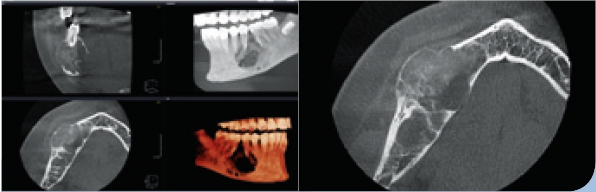

- Die digitale Volumentomographie (DVT) liefert die höchste Auflösung von knöchernen Strukturen, die Darstellung und/oder Differenzierung von Weichgewebe ist jedoch nicht möglich. Vorteile sind die geringen Kosten und die im Vergleich zur CT reduzierten Metallartefakte. Nachteilig hingegen sind der geringe Weichteilkontrast und die Gewebedifferenzierung (Abb. 2 u. 3).

Es ist allgemein bekannt, dass bei der Akquisition einer digitalen Volumentomographie (DVT) mit Artefakten wie Aufhärtungen und Abschwächungen gerechnet werden muss. Obgleich die Rekonstruktionszeit erheblich reduziert wurde, die Auflösung der Aufnahmen immer höher wird und die Bildqualität ständig zunimmt, stellen Artefakte ein stets präsentes Problem in der Verfahrenskette dar. In manchen Fällen machen diese Artefakte gerade für den Ungeübten eine Bildanalyse unmöglich. In der Literatur werden Artefakte wie z. B. Auslöschungs- und Aufhärtungsartefakte beschrieben (Abb.6 u. 7). Sie sind technisch bedingt, während eine andere, sehr wichtige Ursache dieser Artefakte im Patienten selbst zu sehen ist. Da die Belichtung in der Regel mehr als ein paar Sekunden dauert und der Patient im Gegensatz zu der entwicklungsbezogenen These kein statisches Objekt darstellt, kann es passieren, dass er seinen Kopf während der Aufnahme bewegt. In diesem Fall findet man im rekonstruierten Datensatz sogenannte Bewegungsartefakte, die die Bildqualität erheblich beeinflussen können (Abb. 8).

Durch weitere Rechenprozesse können die Daten auf verschiedenste Weise dargestellt werden. Die multiplanaren Rekonstruktionen (MPR) stellen die sinnigste Weiterverarbeitung der Daten dar. Hierbei wird das Volumen durch senkrecht zueinander stehende Ebenen zerlegt, wodurch die Ansichten axial, sagittal und koronal erzeugt werden, ergänzt durch die oberflächengerenderte Ansicht (Abb. 9). Das Angebot entsprechender Bildbearbeitungsprogramme ist vielfältig, zumeist wird das DVT-Gerät mit einer adäquaten Software installiert und eingerichtet – ab diesem Zeitpunkt ist nun der/die Anwender/-in gefordert. In Deutschland ist die Absolvierung eines DVT-Kurses vor Inbetriebnahme eines DVT-Gerätes gesetzlich vorgeschrieben.